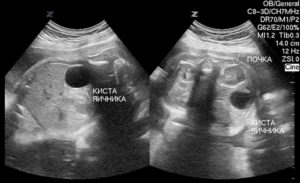

Так как во время беременности заболевание никак не проявляется и не сопровождается никакой симптоматикой, то диагностировать его можно только при плановом УЗИ. Необходимо проходить обследование у квалифицированного специалиста ультразвуковой диагностики, потому что кисту яичника у плода легко перепутать с патологиями кишечника (такие случаи встречались).

Ультразвуковое исследование позволяет не только диагностировать наличие заболевания, но также его локализацию, размеры, эхоструктуру. Также УЗИ дает возможность отслеживать изменения размеров кисты как в сторону увеличения, так и ее регресс.

Благодаря УЗИ можно заранее обнаружить патологию. Киста яичника у плода при подобном обследовании выявляется часто.

Повышенное содержание гормонов в крови будущего ребёнка стимулирует быстрое развитие яичника и одновременно рост кисты в нём. Кисту чаще всего обнаруживают на двадцать шестой неделе.

Врождённая киста может достигать десяти сантиметров. На УЗИ образование хорошо заметно в нижней части живота.

Параметры кисты данного органа варьируются от 1 до 10 сантиметров. Врачи пришли к следующему умозаключению — чаще всего образования формируются у зародыша на 26 неделе беременности. Обнаружить кисту плода можно во время ультразвукового обследования.

Она имеет круглую форму, располагается внизу брюшины зародыша.

Киста яичника у плода — образование, которое сложно рассмотреть во время беременности. Для этого врачи прибегают к ультразвуковому обследованию. Данный метод позволяет им рассмотреть образование в увеличенном виде на мониторе.

Современная ультразвуковая диагностика позволяет не только определить наличие опухоли у зародыша, но еще оценить ее структуру и размеры. На основе этой информации врач может составить прогноз. Чаще всего заболевание проходит спонтанно, за несколько месяцев после родов.